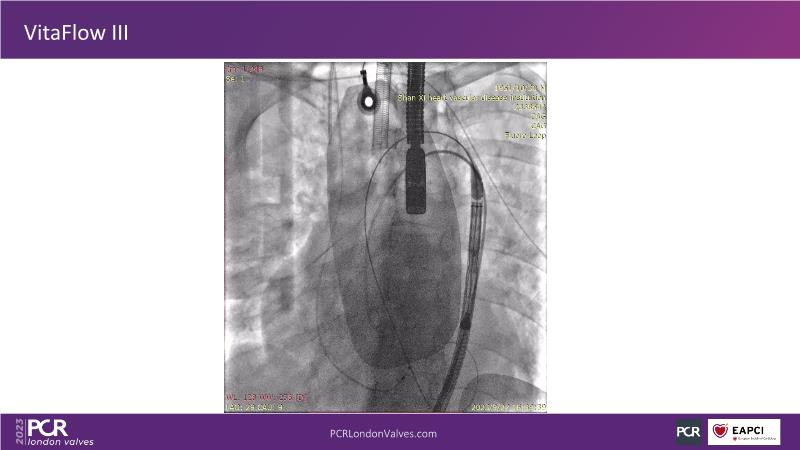

VitaFlow - The electrically enable self-expanding TAVI valve

This session provides insights into the unique design and advantages of VitaFlow Liberty for TAVI. It covers techniques to minimize microdislodgement during the procedure, identifies situations and patient types most suitable for VitaFlow Liberty, and reviews early clinical results associated with this technology.